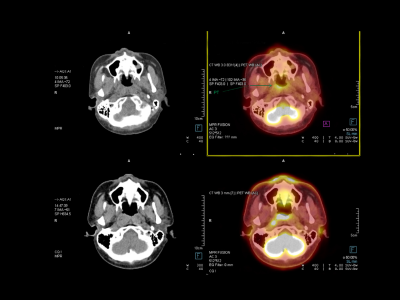

Expert Brain Tumor Diagnosis by Dr. Sanjog Chandana

The first and most important step in your treatment journey is a thorough and accurate diagnosis. Dr. Sanjog Chandana uses state-of-the-art diagnostic techniques to identify brain tumors, which ensures that your treatment plan is based on the most precise information available.

These techniques include:

MRI (Magnetic Resonance Imaging)

A detailed imaging technique that gives an in-depth view of your brain structure and helps detect tumors.

CT Scans (Computed Tomography)

To quickly identify issues such as tumors, swelling, or bleeding in the brain.

Biopsy

In some cases, a biopsy may be required to determine the exact nature of the tumor.

PET Scans

Used to detect the spread of cancer and see how the tumor is affecting other areas.

Dr. Sanjog Chandana’s goal is to make sure you understand every aspect of your diagnosis so that you can make informed decisions about your treatment.